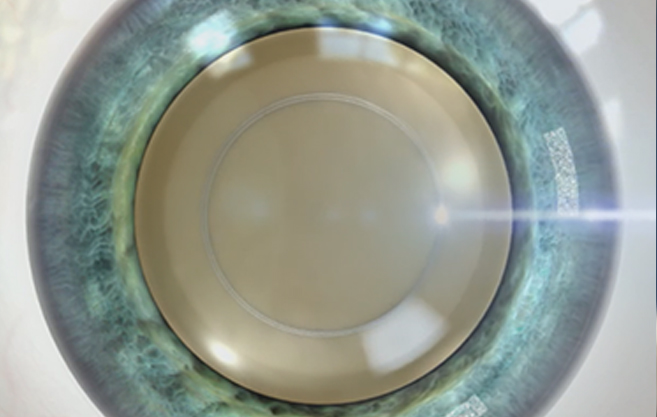

부작용 확률을 낮추고, 수술 성공률을 높이기 위해

수정체 혼탁부위 파쇄시 정교한 파쇄가 필요합니다.

올레이저 노안백내장

균일하고 정교한

레이저 파쇄